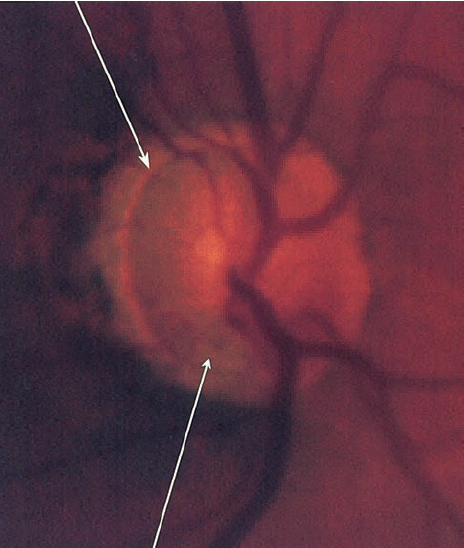

2.2. Gai thị

Tổn hại gai thị không có sự khác biệt với các loại glôcôm khác như tỉ lệ C/D lớn, tổn hại lớp viền thần kinh đĩa thị giác, thay đổi mạch máu của đĩa thị giác…Tuy nhiên, trong glôcôm nhãn áp bình thường tổn hại gai thị cũng có 1 số đặc điểm riêng:

- Lớp viền thần kinh quanh gai thị mỏng hơn so với glôcôm nhãn áp cao.

- Lõm gai không quá sâu và lớp lá sàng ít bị đấy ra phía sau hơn.

- Hay gặp tổn hại viền thần kinh gai thị khu trú ở 1 vị trí kèm theo lõm gai thị sâu và thay đổi lớp lá sàng tạo thành hố gai thị mắc phải, 75% gặp ở glôcôm nhãn áp bình thường so với 15% ở glôcôm nhãn áp cao.

BSVL1

Teo lớp sợi thần kinh quanh gai thị

Mất lớp viền thần kinh

Xuất huyết cạnh gai thị

BSVL2

Lõm gai sâu

Tổn hại gai thị(nguồn: Atlas of Glaucoma)

- Một trong những dấu hiệu thường gặp nhất trong glôcôm nhãn áp bình thường  là teo võng mạc cạnh gai thị ( vùng α và vùng β), tuy nhiên dấu hiệu này không đặc hiệu cho glôcôm nhãn áp không cao .

- Xuất huyết gai thị: rất hay gặp trong glôcôm nhãn áp bình thường.

- Tổn hại lớp sợi thần kinh quanh gai thị: hay gặp tổn hại lớp sợi thần kinh khu trú ở 1 vị trí nào đó hơn là tổn hại toàn bộ chu vi gai thị.

Tuy nhiên,  những dấu hiệu trên không đặc hiệu cho glôcôm nhãn áp bình thường , không cho phép chẩn đoán xác định mà chỉ có giá trị gợi ý glôcôm nhãn áp bình thường  mà thôi.